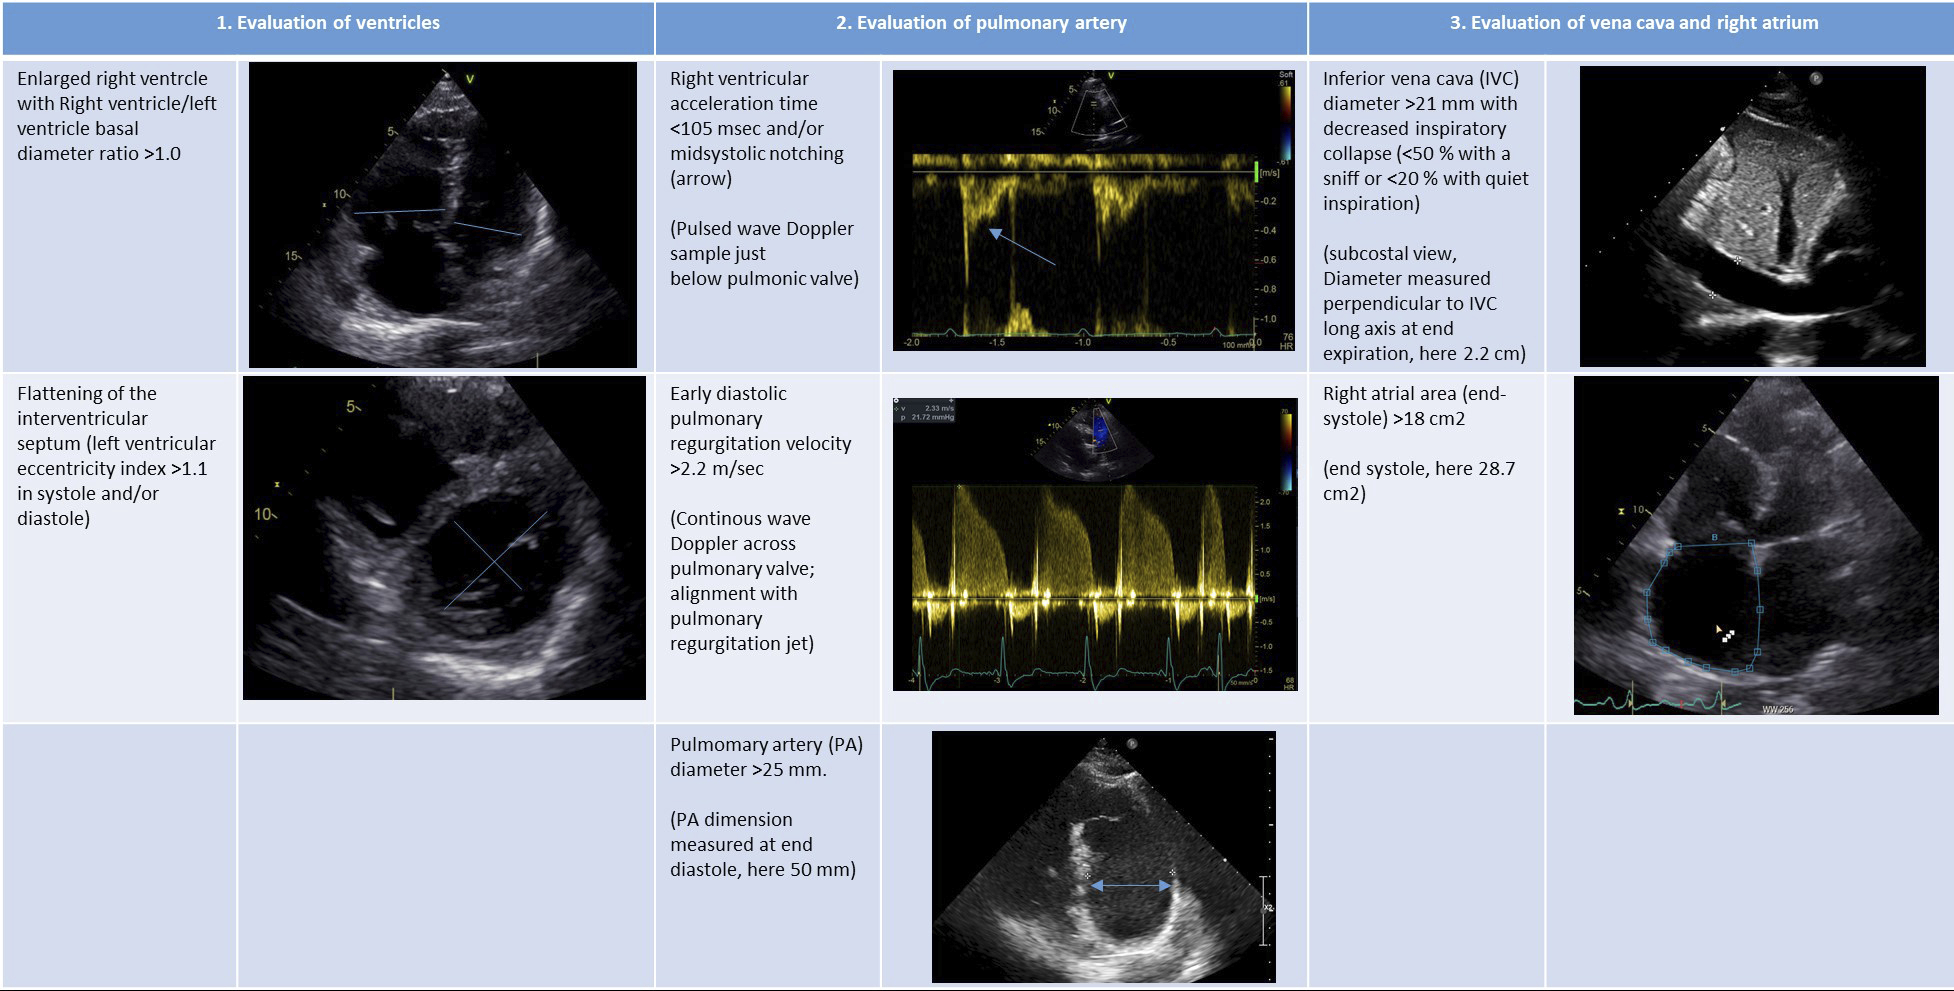

In order to improve the positive predictive value of TTE and given the possibility of missing PH if TRV-based sPAP is underestimated, guidelines recommend looking for indirect signs of PH in the case of normal or moderately elevated TRV [1]. Indirect signs are detailed and illustrated in figure 2 and must be looked for at the levels of the ventricles, PA, inferior vena cava and RA. In all situations except low PH probability, patients should be referred to PH expert centres for further investigations including right heart catheterisation unless they present evident heart or lung disease (suggesting group 2 or 3 PH) compatible with TTE findings (fig. 3) [1, 15].

Figure 2 Indirect signs of pulmonary hypertension at the levels of the ventricles, pulmonary valve / pulmonary artery and inferior vena cava / right atrium. Adapted from Galiè 2016 [1].